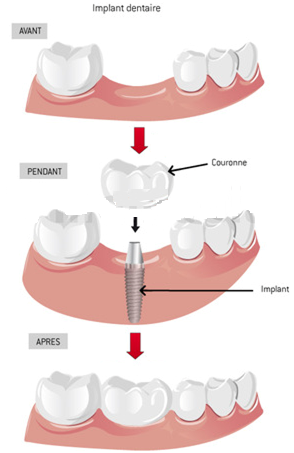

Les implants dentaires réalisés par notre CABINET SAFI SMILE sont des structures qui remplacent les racines des dents naturelles manquantes. Matériellement, l’implant dentaire est une petite vis, installée dans l’os à l’endroit de la dent manquante. Le matériau utilisé est le titane qui est parfaitement biocompatible, aucune intolérance n'a été démontrée à ce jour. De plus, de nombreuses études montrent que l'os vient naturellement se coller au titane. Cela explique le succès de cette technique et l’implant dentaire constitue aujourd’hui, la meilleure solution de remplacement d’une dent manquante. Sur cet implant, la restauration finale sera fixée : une couronne, un pont ou une prothèse complète. Une fois réalisée le patient pourra retrouver l’équilibre masticatoire perdu.

L’implant dentaire étant solidement ancré à l’os, la restauration qu’on fixera sur celui-ci est plus stable qu’une prothèse amovible (partiel ou dentier). Avec des suivis réguliers d’examen nettoyage et une bonne hygiène dentaire, l’implant devient presque permanent.